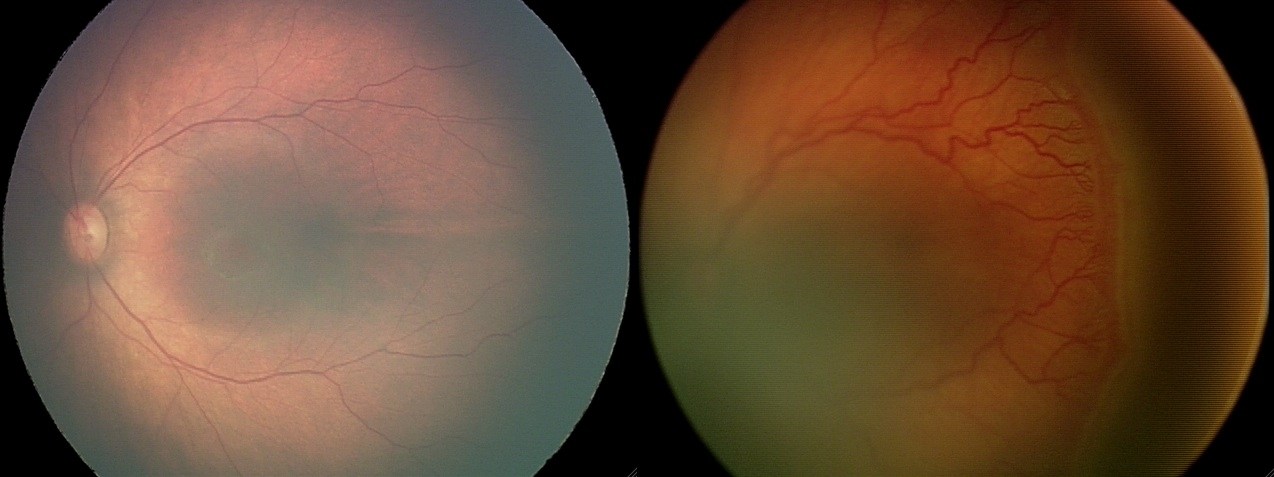

Патология недоношенных детей развивается через несколько этапов, в результате которых может образоваться рубец вместо нормальной сетчатки. Выделяют следующие стадии:

- I стадия – на участках, где происходит разделение клеток сосудов и аваскулярных тканей, появляется белесая линия. При ее выявлении увеличивается частота осмотров ребенка.

- II стадия – отмечается заметное улучшение состояния малыша, хотя на глазном дне могут сохраняться незначительные остаточные явления.

- III стадия – вал, образовавшийся на предыдущем этапе, заполняется фиброзными клетками. В это время стекловидное тело становится более плотным, что приводит к втягиванию сосудов. Риск возникновения осложнений значительно возрастает.

- IV стадия – эта стадия называется термальной, так как состояние ребенка продолжает ухудшаться, и качество зрения резко снижается.

- V стадия – происходит полное отслоение сетчатки, что приводит к практически полной утрате зрения.